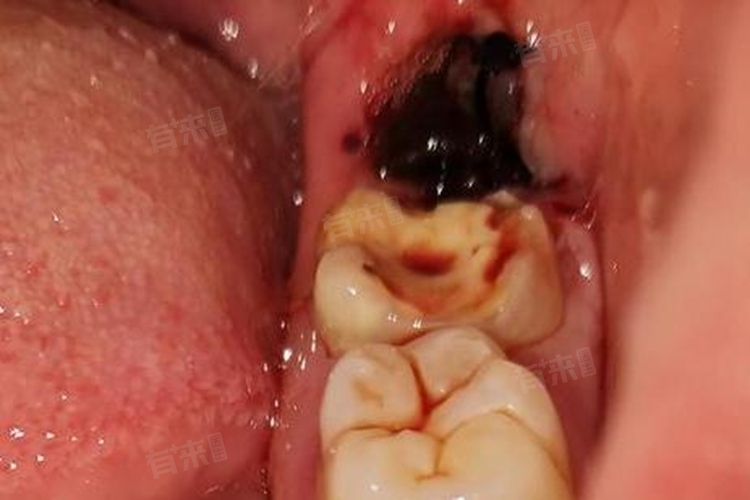

- 若拔牙创口愈合良好(术后7-10天),拆线时基本无痛感,因为此时牙龈组织已初步修复,神经末梢尚未完全长入新生组织中。但对于愈合延迟、存在局部炎症或缝线嵌入牙龈的情况,拆线时可能出现短暂刺痛,但这种疼痛远低于拔牙术后的疼痛程度。复杂拔牙(如埋伏阻生齿)后若采用较粗的不可吸收缝线,拆线时牵拉感可能稍明显,但医生会通过局部涂抹表面麻醉凝胶(如利多卡因)来减轻不适。